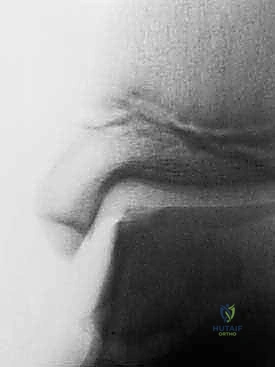

المرحلة الأولى: جراحة الحصاد (Harvesting) والتنظير

هذه المرحلة هي جراحة يوم واحد بسيطة، تُجرى تحت التخدير الموضعي أو العام باستخدام منظار الكاحل بتقنية 4K عالي الدقة.

1. الاستكشاف والتنظيف: يُدخل الدكتور هطيف الكاميرا الدقيقة لتقييم حجم الآفة بدقة، وتنظيف أي أنسجة تالفة أو أجسام حرة داخل المفصل.

2. أخذ الخزعة (Biopsy): يتم أخذ عينة صغيرة جداً من الغضروف السليم (بحجم حبة العدس أو أقل من 200-300 مليغرام) من منطقة غير حاملة للوزن في المفصل (Non-weight bearing area)، بحيث لا يؤثر أخذها على وظيفة الكاحل.